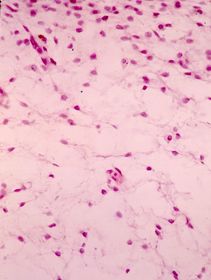

Tejido conjuntivo primitivo. mesénquima

en un feto . Se aprecian el aspecto estrellado de las células mcscnquimatosas y la distribución laxa del tejido